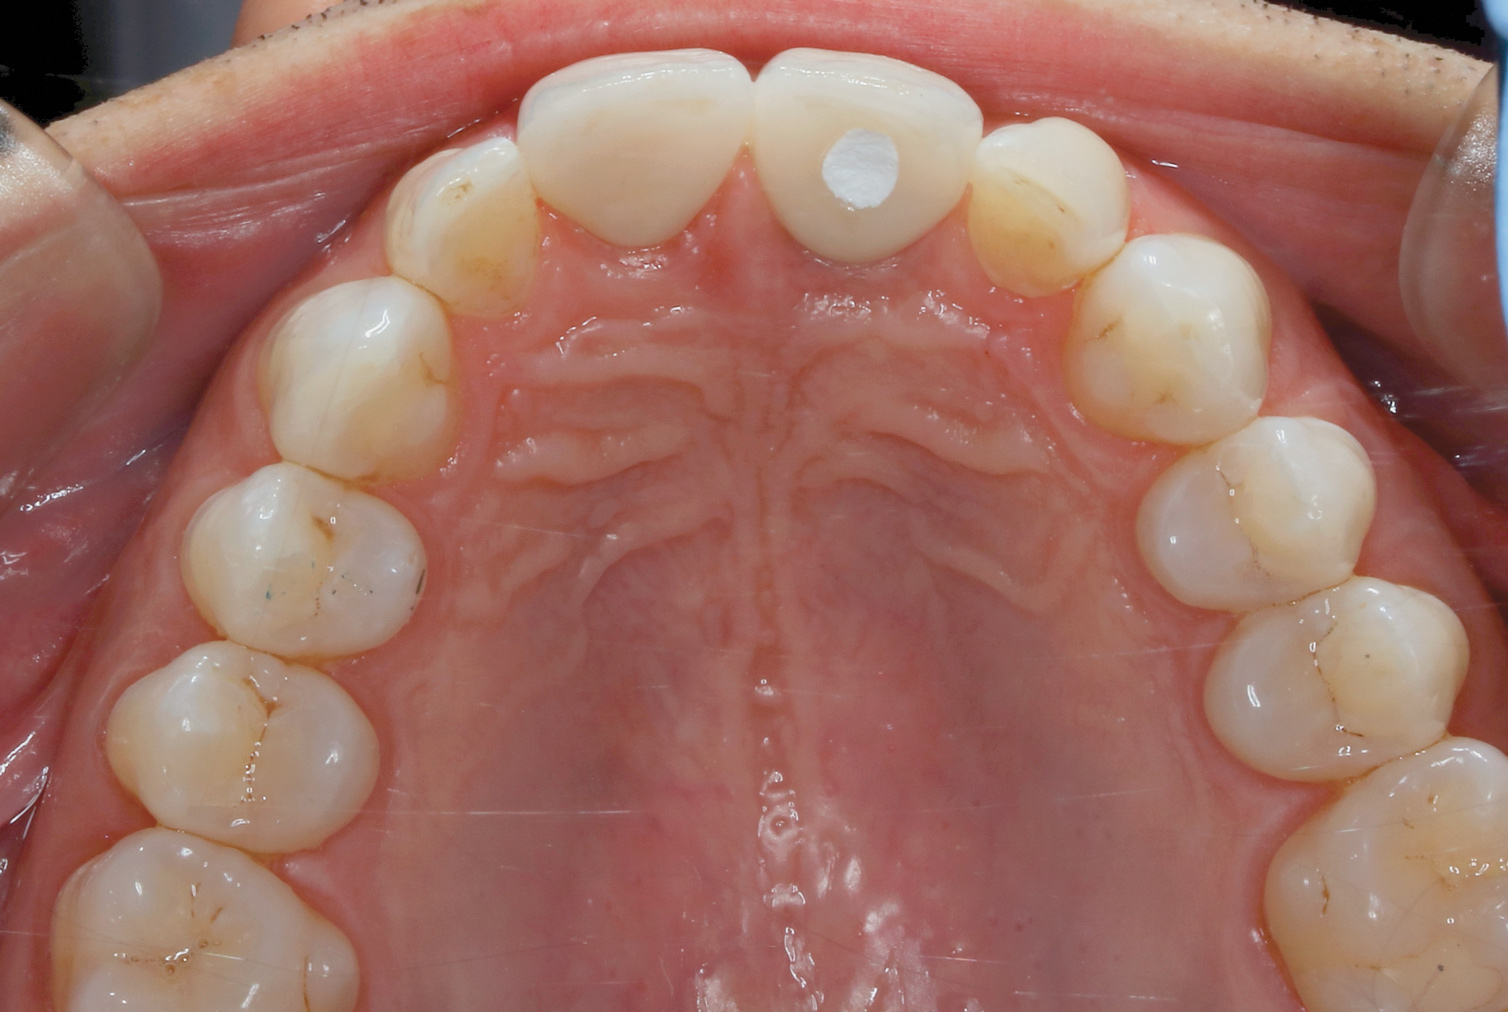

Fig 12. Incisal view (clinical) of crown Nos. 8 and 9.

Figure 12